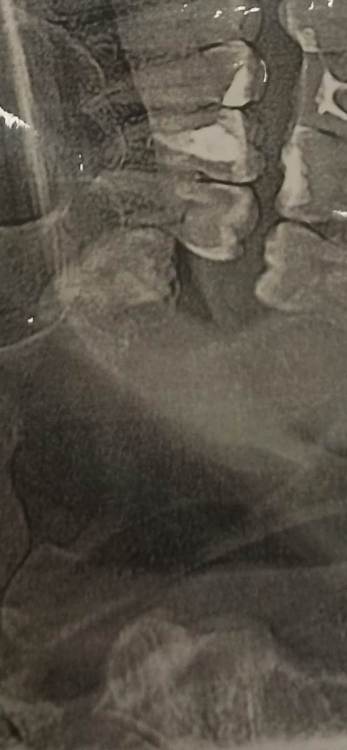

Здравствуйте, подскажите пожалуйста, стоит ли удалять верхние зубы мудрости. Был в двух разных клиниках, в одной сказали, что надо удалять, в другой, что не стоит. Никакого дискомфорта они не вызывают, болей нет. 28 лет. СпасибоScreenshot_2024-03-06-11-13-03-289_com_miui.gallery.thumb.jpg.4c57e196865248069b5846c81165aa65.jpg

В Вашем случае, когда нет нижних восьмерок, верхние абсолютно бесполезны, даже если вылезут и встанут на свое место. Но, находясь в такой позиции велика вероятность, что со временем они будут портить дистальный отдел седьмого зуба, а уж семерки явно жалко. Поэтому смысл убрать восьмерки в профилактических целях есть. Но профилактика тоже штука не стопроцентная. У кого-то такой зуб всю жизнь сидит в этом месте и нет никаких проблем, а у кого-то удаляют и семерка все равно с кариесом оказывается. Поэтому решайте сами.